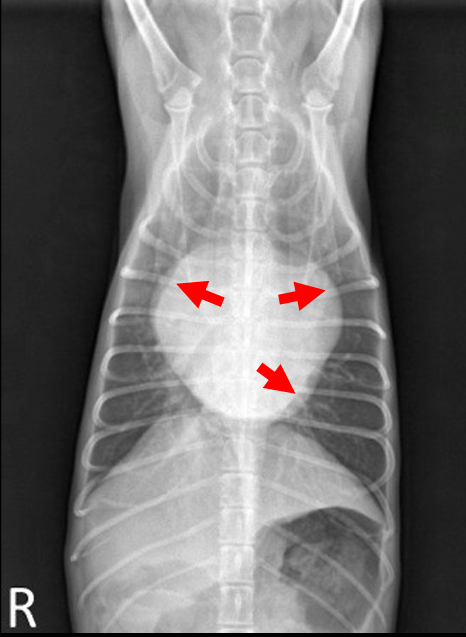

| MVI + CTR (CTR = chordae tendineae rupture), bivalvular |

| - Mitral & Tricuspid valve 모두 이상 ⇒ Lt. & Rt. atrium 모두 볼록 - Lt. auricle, LA 확장 ⇒ Trachea elevation, Caudal waist 소실, tall heart ☑️ 흉수(pleural effusion) : 우심부전 시 주로 흉수, 복수 (체순환 혈액 받아들이지X) : 우심 valve 이상 → 폐로 가는 혈액량 감소 → 우심방 비대, 혈액 정체, congestion → 전신 정맥압 상승 → pleural cavity의 모세혈관 압력 증가, 수분 누출 → 흉막강에 체액 축적 ⇒ 심장 주위 뿌옇게 물 참. 흉수 때문에 폐가 팽창하지 못해서(collapsed), 빈호흡, 호흡곤란, 산소 포화도 감소, 청색증 (*Thoracocentesis 필요) ☑️ 폐수종(pulmonary edema), 폐출혈 : 주로 좌심부전과 연관 (폐순환 혈액 받아들이지X) : 폐정맥압, 폐모세혈관압이 상승(pulmonary vein hypertension) → 물이 빠져나와 폐포 공간으로 축적. : pulmonary vein, post capillary hypertension → 압력 너무 높아져서 터지면 폐출혈 ☑️ 호흡을 잘 못해서 위에 공기가 참 (Airophagia) ☑️ Heart failure → cardiac output 감소, hypotension(동맥), 기침, 기절 등 |

| 영상학적 소견 - interstitial pattern - Cardiac sillouette (심장 주변에 물이 차서 심장이 잘 안 보임) - Scallop sign (중력에 의해 물이 아래로 가라앉아 뿌옆게 보이고, 심장이 잘 안 보임) |